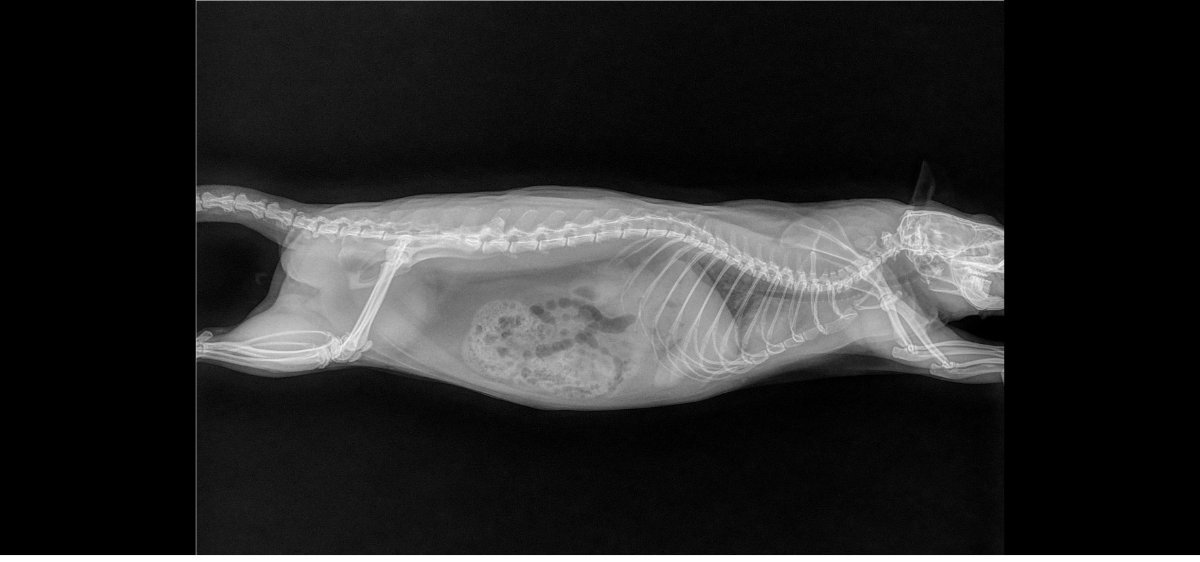

pas de super bonnes nouvelles car les deux miss ont les poumons atteints, si je m'en doutais un peu pour Izar qui ronflait depuis mars (c'est vite parti avec le collyre dans le nez) et respirait une peu trop vite, je suis tombée des nues pour Thari, qui me fait un coup à la Seren : zéro symptôme mais poumons pourris (si seulement elle pouvait avoir la même longévité :siffle:). Les deux pupuces sont donc sous deux antibiotiques (un par injection et un par voie orale) et Izar à en plus un AINS. Contrôle radio prévu dans quelques semaines.

Petites photos des belles et radios en spoil

Izar

Izarfaceavril2023.jpg.5285a5abdd7060aa126244520459ef3c.jpg

Izarprofildroitavril2023.jpg.31a414688eda128425e73b46a0b65f38.jpg

Izarprofilgaucheavril2023.jpg.0eec5561fec0efb202ff549e6a77de8f.jpg